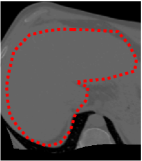

An example of CT/CBCT and MR/CBCT registration results are shown in figures 3 and 4, respectively. For both cases, the CBCT image (first column) was acquired intra-operatively after needle insertions and was employed as a reference for image registration. The pre-operative image is displayed before registration (second column), after PM-EA (third column) and after PM-EA+Evo (fourth column). The occurrence of patch shifts is reported for each spatial direction in panels (m–o): for each histogram, the shift with maximal occurrence is shown by the red dashed line. For panels (a–l), a ROI — manually defined on the CBCT image/encompassing the liver — is shown using red dash lines. Our visualization shows an improved correspondence of the contour of the liver with the manually defined liver boundary when the PM-EA solution is employed (see 3(c,g,k) and 4(c,g,k)). Moreover, an even better correspondence of the contour is observable using the PM-EA+Evo solution (see 3(d,h,l) and 4(d,h,l)).

Trans.

[X-Y]

CBCT

(a)

CT / No registration

(b)

CT / PM-EA

(c)

CT / PM-EA+Evo

(d)

Sag.

[X-Z]

(e)

(f)

(g)

(h)

Cor.

[Y-Z]

(i)

(j)

(k)

(l)

(m)

(n)

(o)